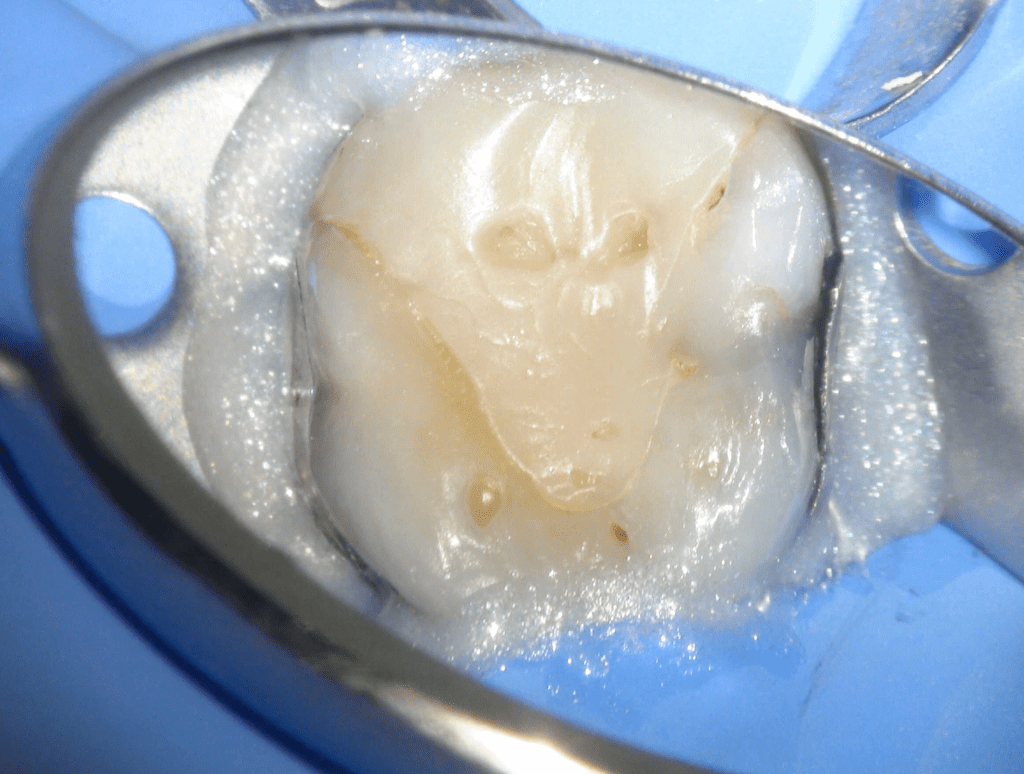

Fisura, remoción amalgama para explorar